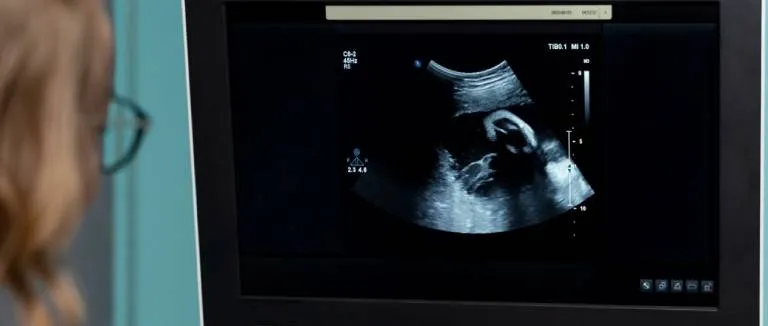

Dış Gebelik (Ektopik Gebelik) Nedir?

Dış gebelik gebelikle birlikte rahim içine yerleşmesi gereken döllenmiş yumurtanın, rahim dışındaki fallop tüplerinde geliştiği bir durumdur.

Dış Gebelik Nedir? Dış Gebelik Belirtileri ve Nedenleri

Dış gebelik, döllenmiş yumurtanın rahim içine yerleşmesi yerine genellikle fallop tüpleri bölgesinde bir yere yerleşmesi ile görülen bir rahatsızlıktır.